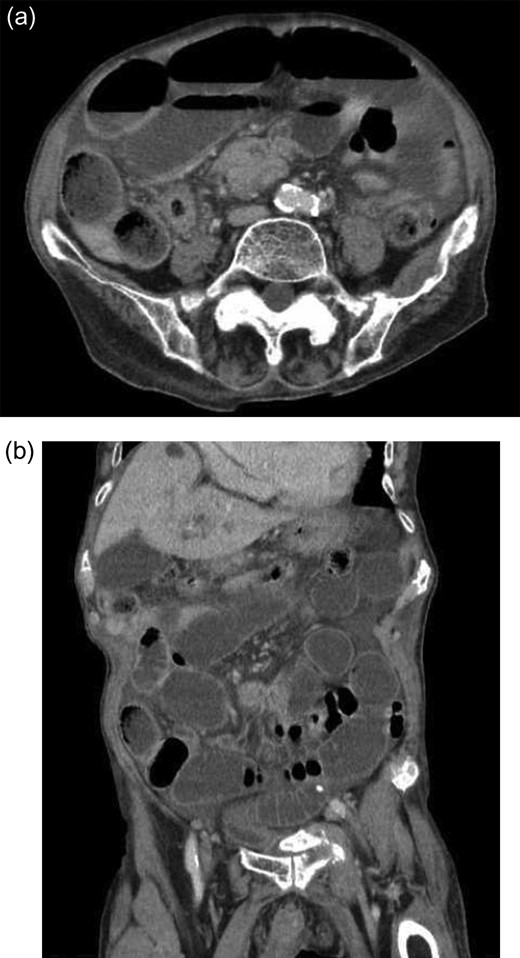

An 88-year-old Japanese man presented with abdominal pain, distension, and appetite loss that exacerbated over the last 4–5 days. He also experienced intermittent vomiting prior to hospital admission. His past medical history included myocardial infarction treated with percutaneous catheter intervention, and he was receiving aspirin (100 mg/day) and lansoprazole (15 mg/day). Upon physical examination, the abdomen was diffusely distended and tender; however, there were no signs of peritoneal irritation such as rebound tenderness or muscle guarding. His vital signs were within the normal limits. Laboratory tests revealed slightly elevated inflammatory markers and anemia (white blood cell count: 4400/μL; hemoglobin: 11.4 g/dL; C-reactive protein: 3.189 mg/dL), but tumor marker levels were not elevated (carcinoembryonic antigen: 1.7 ng/mL; carbohydrate antigen 19-9:6.3 U/mL). Computed tomography showed a distended ileum that adhered to the cecum with thickened walls (Fig. 1a and b). There was no evidence of free air, massive ascites, intestinal ischemia or mesenteric torsion. Thus, he was diagnosed with SBO, and a nasogastric tube was inserted to decompress the upper gastrointestinal tract. However, his symptoms continued to persist. We subsequently performed exploratory laparotomy 2 days after admission and detected diffusely dilated intestines and an inflamed cecum that adhered to the ileum. Iliocecal resection including D2 lymph node dissection was accomplished after we took into account the possibility of malignancy. Ileum-ascending colon anastomosis was performed with functional end-to-end anastomosis by using Endo GIATM Reload with Tri-stapleTM Technology (purple 60 mm; Covidien, USA).

(a and b) Computed tomography showing the distended ileum that adhered to the cecum with thickened walls. There are no signs of free air, massive ascites or intestinal ischemia.